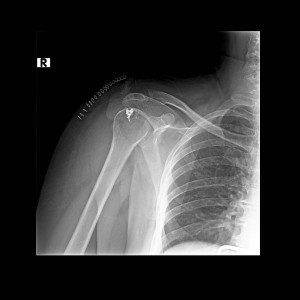

Yırtığın tesbiti Yukarıdaki bulgulardan herhangi biri mevcutsa zaman geçirmeden doktora başvurun. Şikayetleriniz, hastalığın gelişme öyküsü ve dikkatli bir muayene ile önemli ölçüde fikir sahibi olunabilir. Röntgen incelemesi kemik kaynaklı bulguların tesbitinde yararlıdır. Ancak rotator manşetin direkt izlenebildiği MR ve ultrasonografi gibi tetkikler genellikle kesin tanı ve tedavinin planlanması için gereklidir.